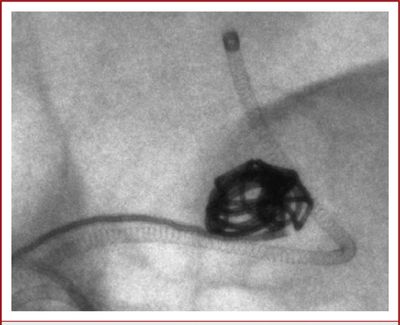

A DSA image shows a clot was placed & retrieved with a stent retriever from the left MCA.